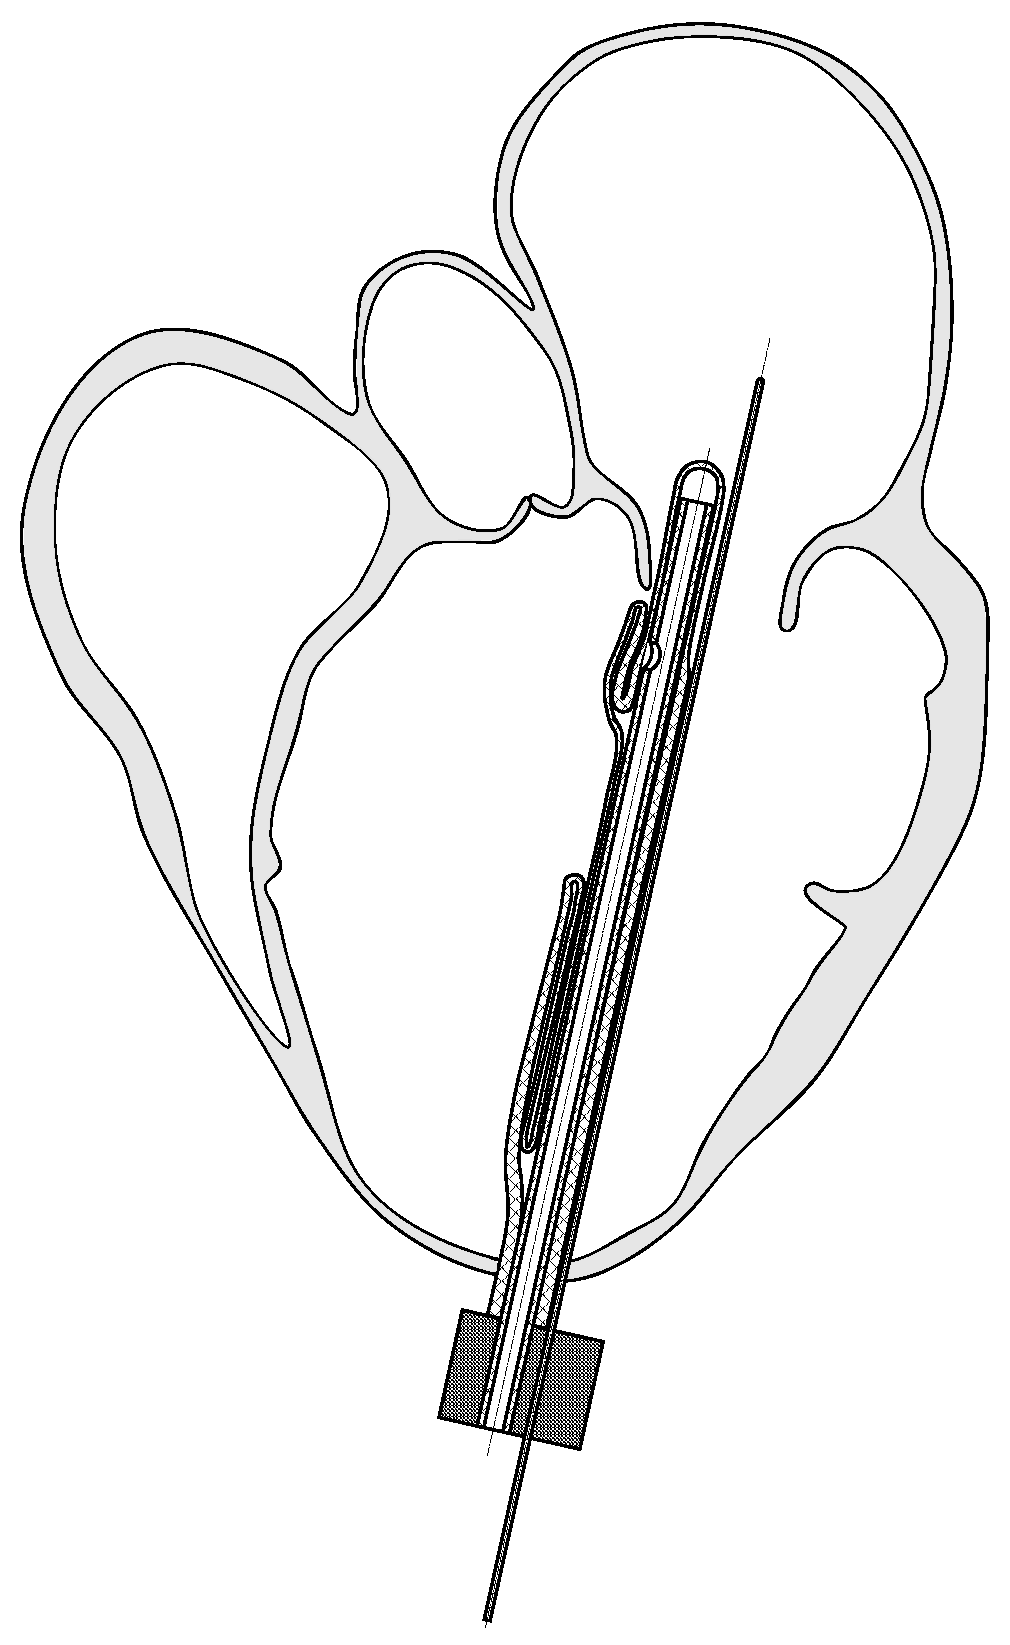

2. Implantable Left Ventricular Assist Device

- PCT Application, Implantable Left Ventricular Assist Device and System for Ventricular-assist for Use in Patients with End-Stage Heart Failure PCT/PL2021/050004. Available online: https://patentscope.wipo.int/search/en/detail.jsf?docId=WO2021162564 (accessed on 28 May 2023).

- Tesch, K.; Jasinski, R.; Dabrowski, L.; Rogowski, J. Experimental investigation of the performance of an innovative implantable left ventricular assist device—Proof of concept. Appl. Sci. 2023, 13, 973. [Google Scholar] [CrossRef]